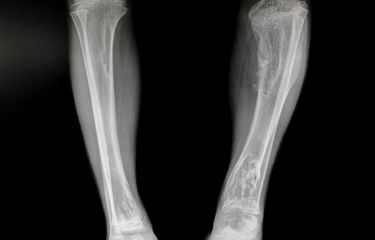

Sindrom ini memiliki tiga tanda klinis yaitu, displasia fibrosa, pigmentasi kulit (cafe-au-lait), dan disertai puibertas prekoks.

Baca juga: Displasia Fibrosa

- Patah tulang

- Jaringan seperti bekas luka di tulang (displasia fibrosa).

Kelainan tulang (displasia fibrosa) terkadang harus diobati dengan pembedahan.